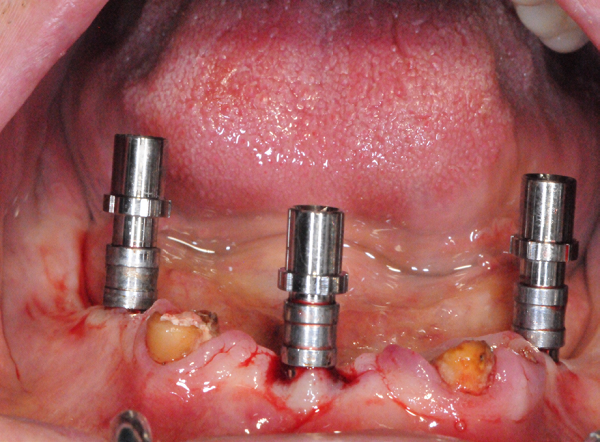

Figure 1: Three mini implants inserted in patient’s jaw. Mini-implants remain during the complete procedure as fixed reference points. In this way, the prosthetic guide can be inserted in a reliable and reproducible manner during the CT imaging as a future surgical template when screwed onto the mini-implants.

figure 1